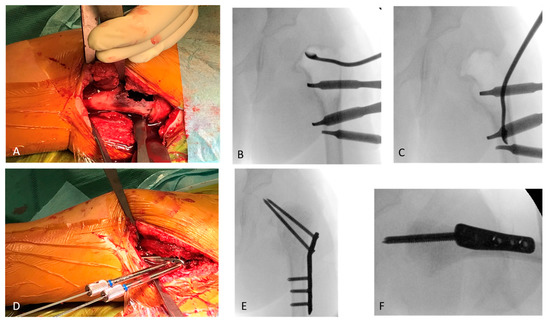

Stabilisation of Pathologic Proximal Femoral Fracture near the Growth Plate with Use of a Locking Plate and Transphyseal Screws

2.1. Case Report